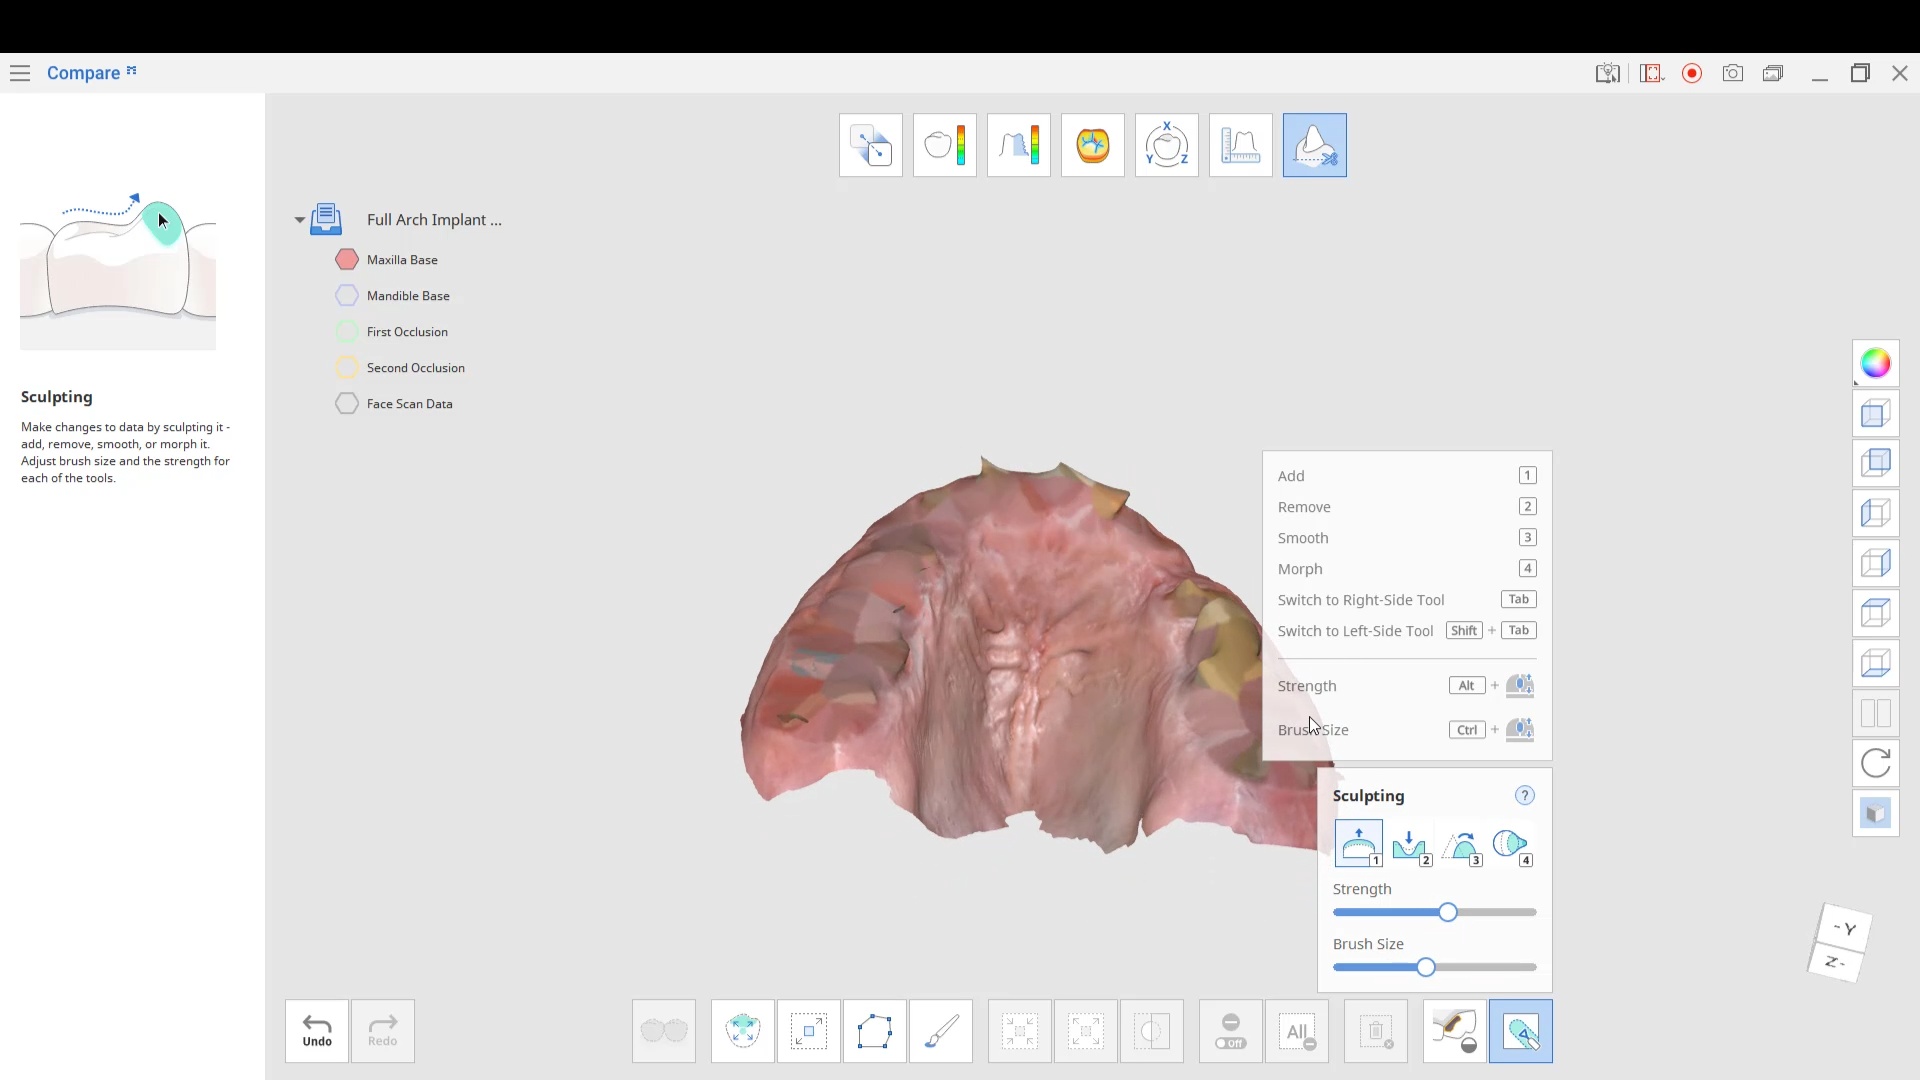

Full Arch Implant Planning Set Up with Medit i700

This used to be such a long process and we can bust them out in no time. take upper and lower scans in a minute. add lip…